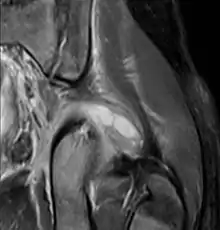

| Transverse T2 magnetic resonance imaging section through the hip region showing abscess collection in a patient with pyomyositis. | |

| Diagnostic method | Diagnostic method used for PM includes ultrasound, CT scan and MRI. Ultrasound can be helpful in showing muscular heterogeneity or a purulent collection but it is not useful during the first stage of the disease. CT scan can confirm the diagnosis before abscesses occur with enlargement of the involved muscles and hypodensity when abscess is present, terogenous attenuation and fluid collection with rim enhancement can be found. MRI is useful to assess PM and determine its localization and extension |